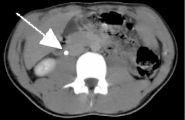

Left image is a pre-contrast transverse image showing a 3 mm calculus (arrow) in the region of the right ureter anterior to the psoas muscle.